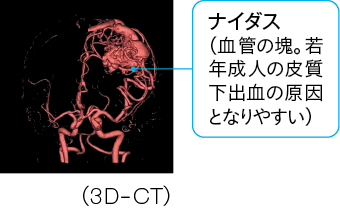

*2【脳動静脈奇形(arteriovenous malformation、AVM)】=通常、動脈と静脈の間には毛細血管があるが、脳動静脈奇形は毛細血管がなく、nidus(ナイダス)と呼ばれる拡張・蛇行した血管の塊が見られる(図5)。脳動静脈奇形は20~40歳の若年成人に多いため、若年成人の脳出血では脳動静脈奇形を疑って、造影CTやMRI、脳血管造影などの検査を進めていく必要がある。

図5 脳動静脈奇形(AVM)